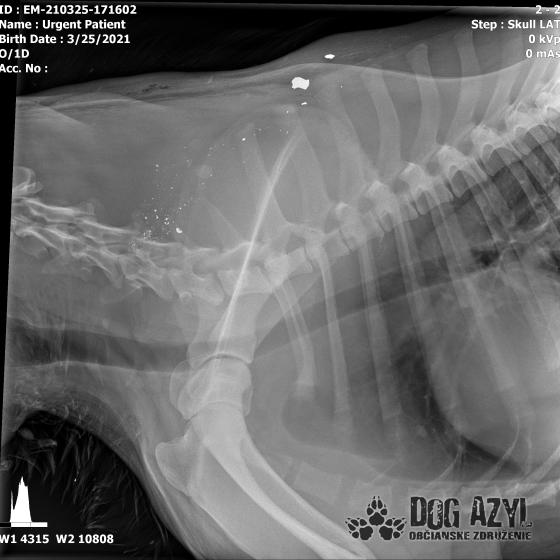

Strela zasiahla Barisa v oblasti lícnej kosti, ktorá mu rozdrvila sánku a následne putovala cez krk až po krčnú chrbticu. Úlomky z guľky (neviem ako sa to odborne volá) sa roztrieštili na "milión" kusov počas svojej cesty. Tieto úlomky sú všade (ako vidieť aj na RTG). Jeden (alebo niekoľko týchto úlomkov) sa dostali až po miechu, ale našťastie ju neprerazili. Toto spôsobilo, že Baris citlivosť v nohách na ľavej strane sice má, ale má poškodenú motoriku. Tieto úlomky sa z oblasti stavcov, miechy aj krku dnes odstránili, ale Barisko z ďaleka nemá vyhraté. Miecha je totiž zakrvácaná (opäť sa ospravedlňujem za nepresnosť a laickosť) a to, že ako veľmi je poškodená, alebo či jeho slabosť bola spôsobená "iba opuchom" sa ukáže cca do 24 hodín. Ak Baris nedajbože do zajtra stratí citlivosť v nohách, tak.. žiaľ... Ale! ak citlivosť zostane, prípadne nastane aj zlepšenie, tak vzplanie plamienok ďalšej nádeje a bojujeme ďalej!